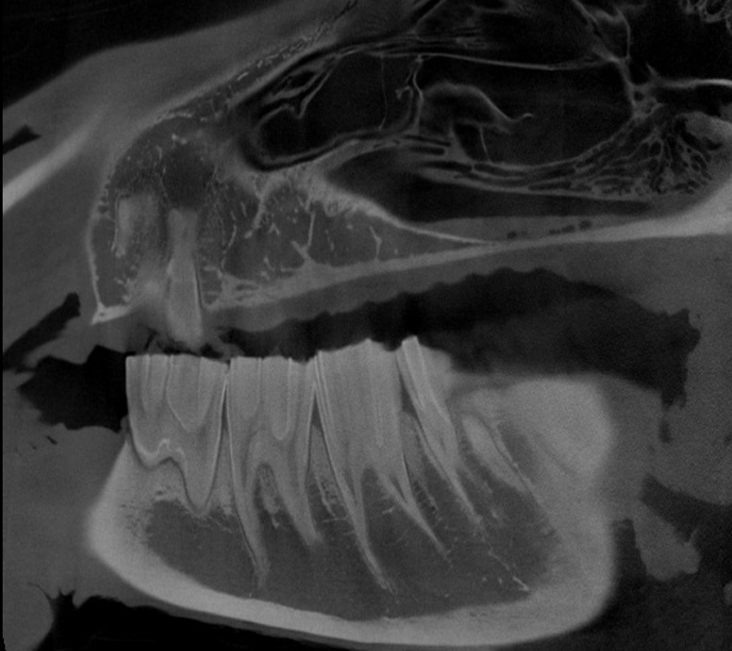

Our High Definition Volumetric Imaging (HDVI) technology represents the most advanced stage of Flat Panel CT technology. It offers exceptional diagnostic imaging for both hard and soft tissues, in diagnostic settings and intraoperative theaters. It is the gold standard for orthopedic applications.

Pegaso enhances safety and usability by enabling the scanning of a standing horse’s head, neck, and limbs.

Scan of the standing horse

Pegaso scans head, neck and limbs of the standing horse